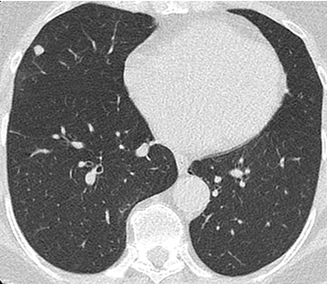

Beispielhafte Aufnahmen verschiedener Erkrankungen

(Lungenklinik Lostau)

Die Computertomographie (CT) liefert detaillierte Querschnittsbilder und ist zentral für die Abklärung vieler Erkrankungen der Lunge und des Brustkorbs – zum Beispiel bei unklarer Luftnot, Tumorverdacht, entzündlichen Veränderungen oder zur Verlaufskontrolle. Je nach klinischer Fragestellung kann die CT auch angrenzende Regionen einbeziehen (zum Beispiel Oberbauch bei Staging-Fragestellungen).